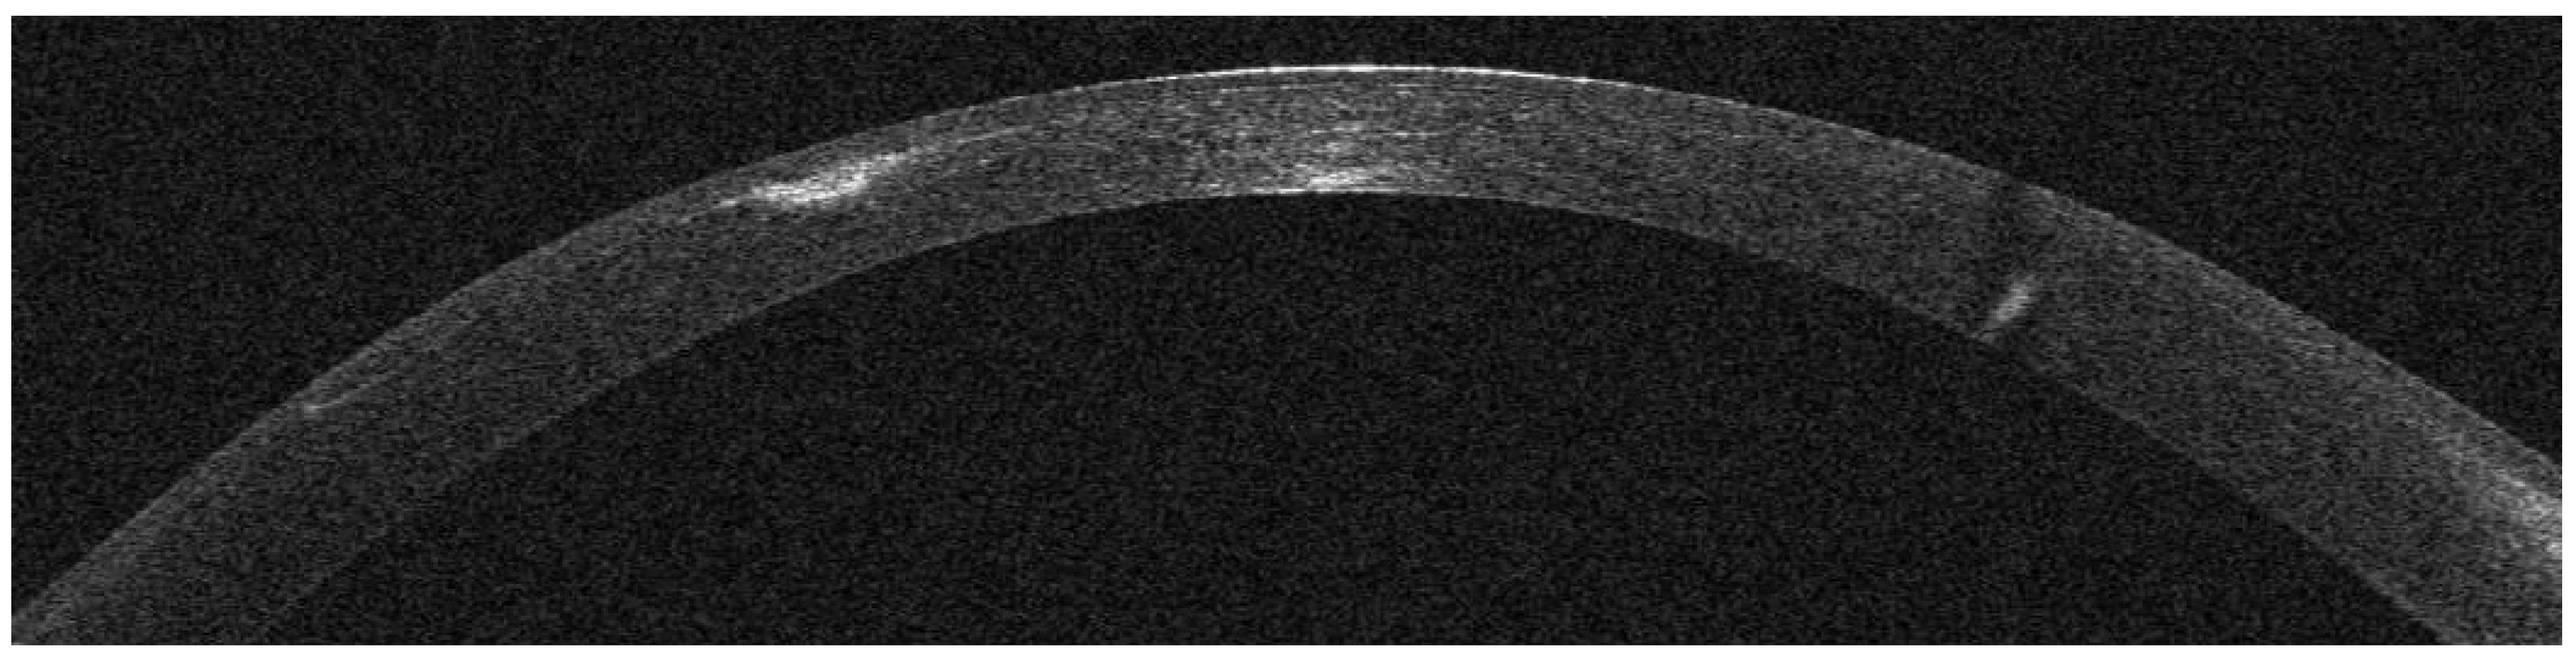

AS-OCT Features

Infectious Keratitis Post-KLEx

Patient #3

Patient #4